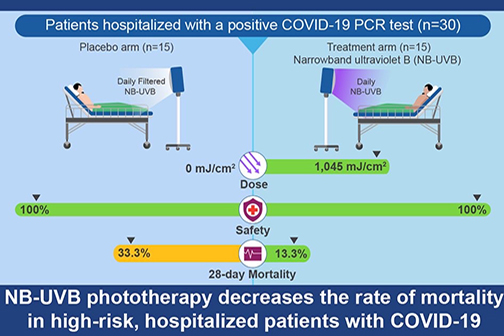

LSU Health Study Shows Promise of NB-UVB Phototherapy in Hospitalized COVID-19 Patients

A randomized, placebo-controlled pilot study led by Frank Lau, MD, FACS, Associate Professor of Clinical Surgery at LSU Health New Orleans School of Medicine, has found that narrow-band ultraviolet B (NB-UVB) phototherapy is safe and decreased death in a small group of patients hospitalized with COVID-19. More